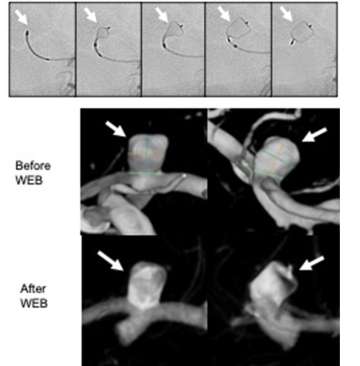

Figure 6. Intrasaccular flow disruption of an ICA terminus aneurysm using the WEB device. Top panel demonstrates sequential images from left to right showing deployment and finally detachment of the WEB device

Intrasaccular flow disruption: This technique involves placement of a special braided mesh device (for example, the WEB device) inside the aneurysm in order to block blood flow into the aneurysm. This technique is especially good for aneurysms located at branch points in the vessel, so called bifurcation aneurysms (Figure 6).